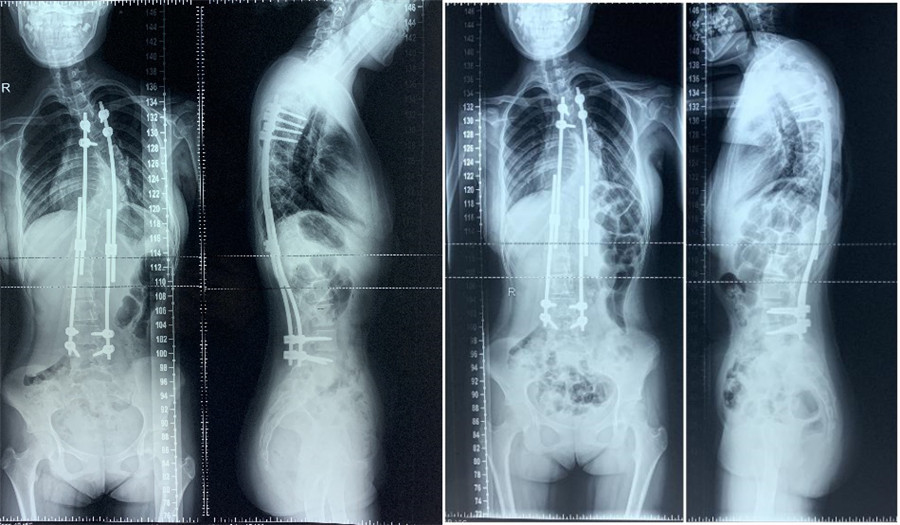

2019年06月第2次生长棒延长术 2020年01月复查